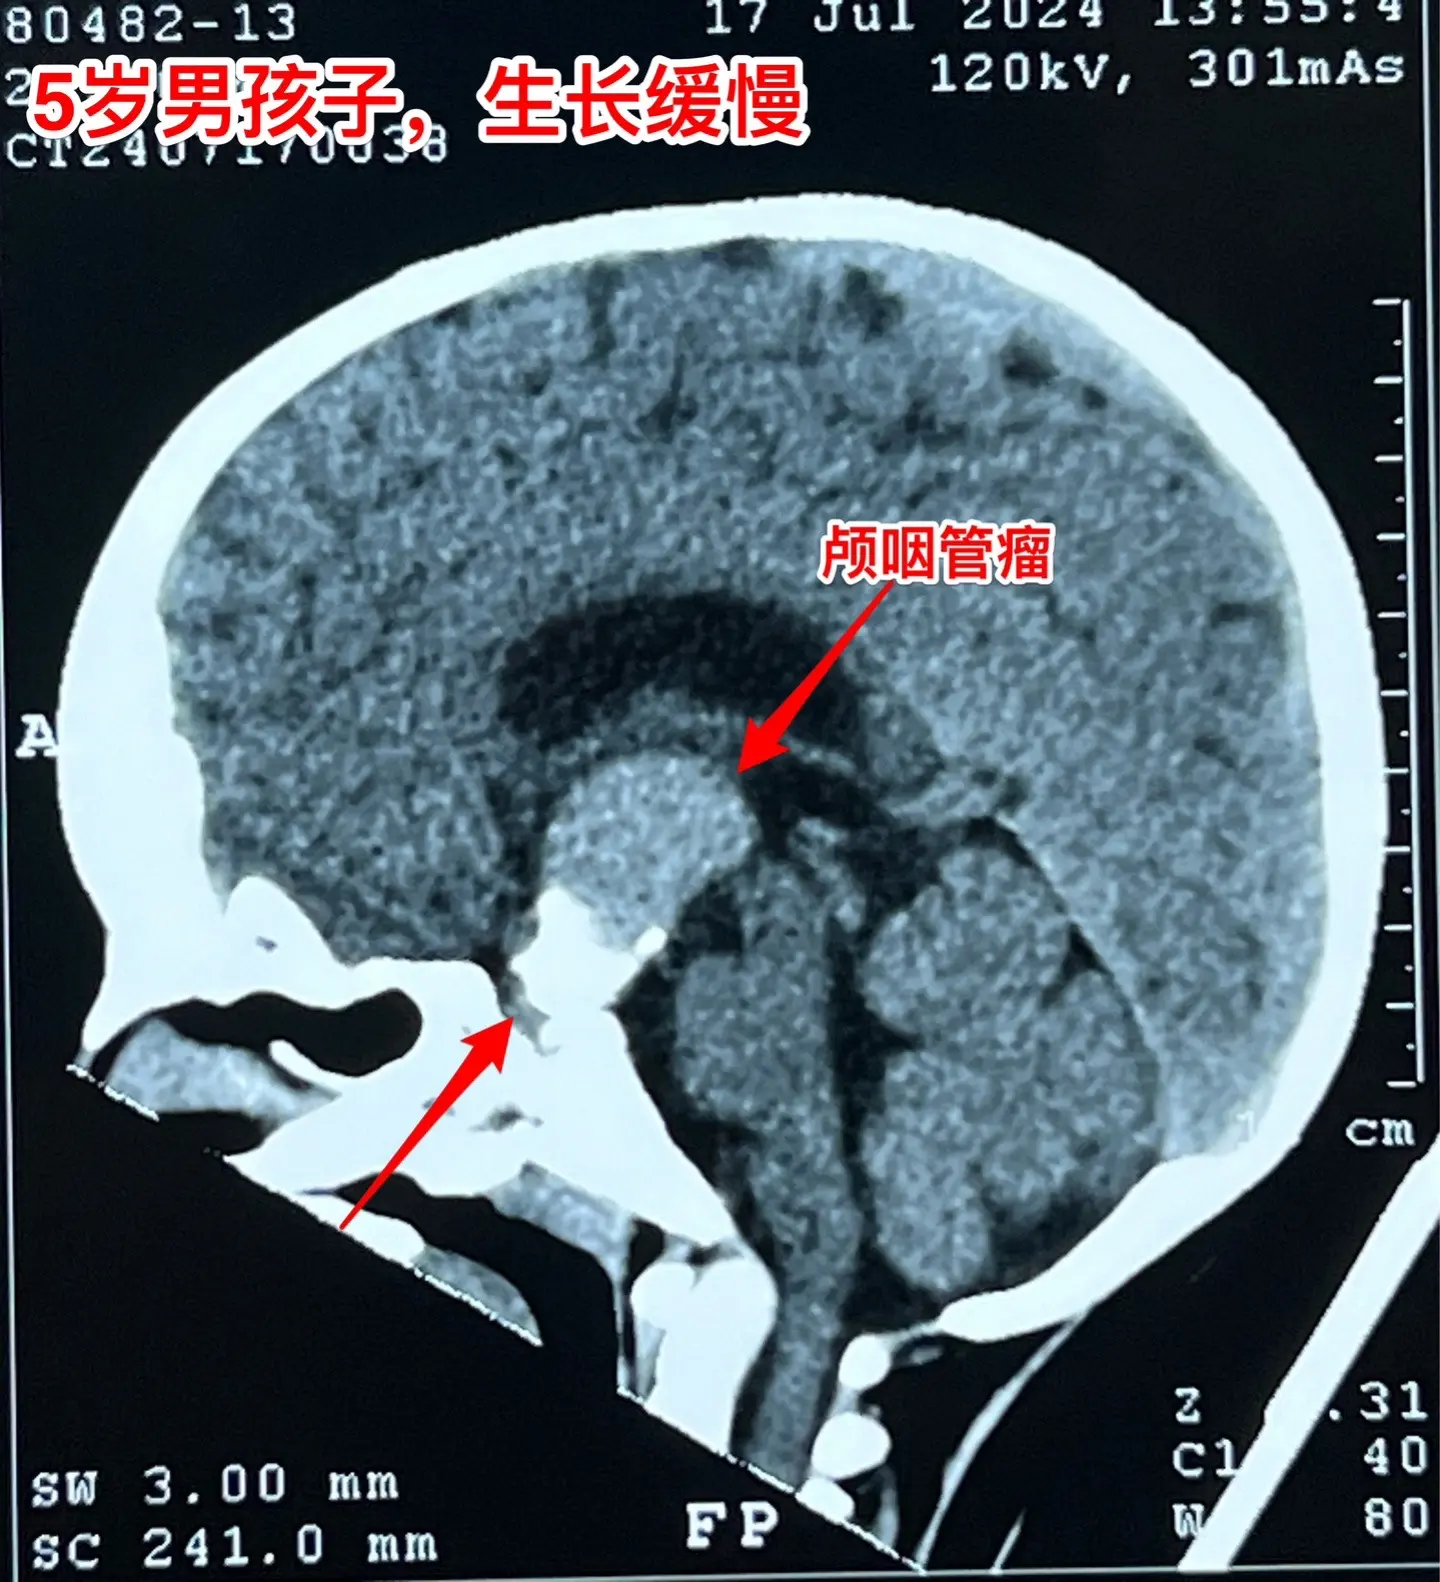

一天两台颅咽管瘤手术对于我们科是常态!7月24日我们科按常规安排了两台颅咽管瘤:第一个5岁男孩子,广东人,因为身高增长缓慢发现了颅咽管瘤。第二个是25岁的三门峡市男性,因为视力下降发现了颅咽管瘤。两个手术都顺利完成。 这样的手术安排对于我们三博脑科医院神经外科八病区来说几乎是常态。有时候一天完成两台复发颅咽管瘤手术,最多的时候一天完成三台颅咽管瘤手术。应该说如果一天只作一个颅咽管瘤手术是比较合理的,一天作两个劳动强度是很高的,不值得提倡。